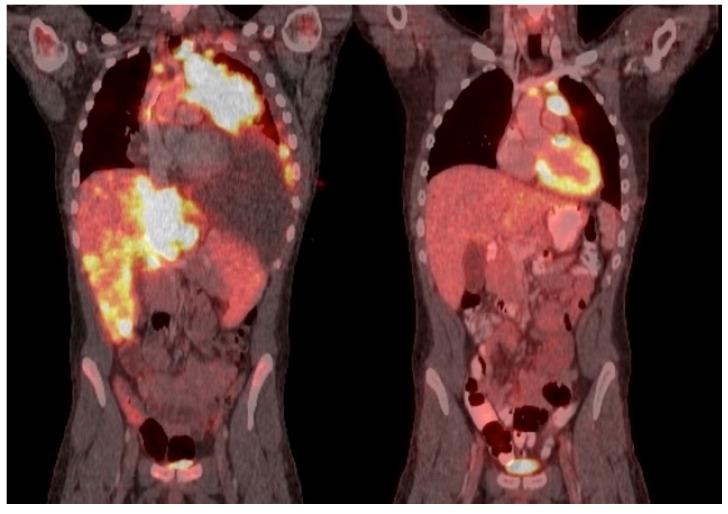

Venetoclax is approved for adult patients with chronic lymphocytic leukemia and acute myeloid leukemia. Expanding its use to the pediatric population is currently under investigation, but more robust data are needed. We retrospectively analyzed the safety and efficacy of venetoclax in children/AYA with ALL/LBL. We identified 18 patients (T-cell ALL, = 7; T-cell LBL, = 6; B-cell ALL, = 5) aged 6-22 years. No new venetoclax safety signals were identified; the most common toxicity was myelosuppression. No deaths occurred within 30 days from the start of the therapy. A mean of 2.6 (range 0-8) prior lines of therapy were given. The mean duration of venetoclax was 4.06 months (range 0.2-24.67 months). Complete remission was achieved in 11 (61%) patients. Of the eight patients who remain alive, four are continuing on venetoclax combination therapy, and four proceeded to hematopoietic stem cell transplantation. Three patients who initially achieved CR, later relapsed, and are deceased. Nine patients are deceased, and one patient was lost to follow-up. Overall survival is 9.14 months (range 1.1-33.1), and progression-free survival is 7.34 months (range 0.2-33.1). This is the largest cohort of pediatric/AYA patients who received venetoclax for ALL/LBL. Our data support the consideration of venetoclax-based regimens in pediatric patients with R/R ALL/LBL and its investigation as upfront therapy for T-cell ALL/LBL.

维奈克拉已被批准用于治疗成年慢性淋巴细胞白血病和急性髓系白血病患者。目前正在研究将其应用扩展至儿科人群,但还需要更有力的数据。我们回顾性分析了维奈克拉在儿童/青少年急性淋巴细胞白血病/淋巴母细胞淋巴瘤患者中的安全性和疗效。我们纳入了18例年龄在6至22岁之间的患者(T细胞急性淋巴细胞白血病7例;T细胞淋巴母细胞淋巴瘤6例;B细胞急性淋巴细胞白血病5例)。未发现维奈克拉新的安全信号;最常见的毒性是骨髓抑制。治疗开始后30天内无死亡病例。平均给予过2.6(范围0 - 8)线的前期治疗。维奈克拉的平均使用时长为4.06个月(范围0.2 - 24.67个月)。11例(61%)患者实现完全缓解。在8例存活患者中,4例继续接受维奈克拉联合治疗,4例进行了造血干细胞移植。3例最初达到完全缓解的患者后来复发并死亡。9例患者死亡,1例失访。总生存期为9.14个月(范围1.1 - 33.1),无进展生存期为7.34个月(范围0.2 - 33.1)。这是接受维奈克拉治疗急性淋巴细胞白血病/淋巴母细胞淋巴瘤的最大儿科/青少年患者队列。我们的数据支持考虑在复发/难治性急性淋巴细胞白血病/淋巴母细胞淋巴瘤的儿科患者中使用基于维奈克拉的方案,并支持将其作为T细胞急性淋巴细胞白血病/淋巴母细胞淋巴瘤的一线治疗进行研究。